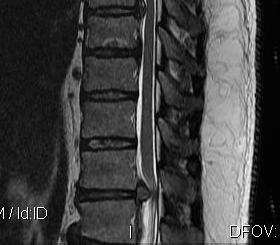

MRI

Very sensitive

- 40% incidence asymptomatic thoracic disc protrusion